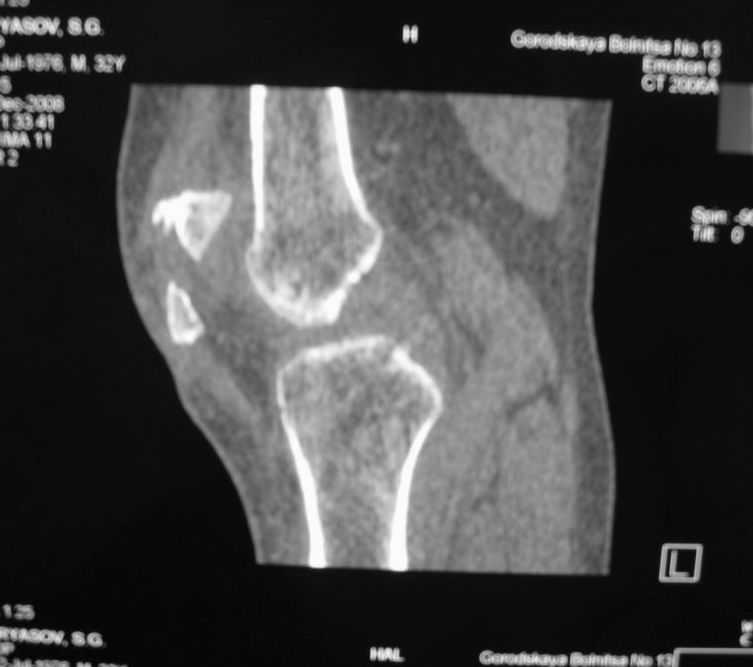

Оскольчатый перелом надколенника

Уважаемые коллеги! Обратился пациент 32 лет с травмой коленного сустава от июля 2008 года

- падение с мотоцикла, прямой удар передней поверхностью коленного сустава. Диагноз - открытый оскольчатый перелом надколенника. В одной из больниц города выполнили ПХО, шов надколенника лавсаном. Заживление раны с частичным нагноением(разведена на участке 3 см). Сейчас мягкие ткани в порядке. R-снимки, КТ в приложении. Объем движений 0/0/110 гр.Ходит почти без хромоты.

Жалобы на торчащий под кожей один из отломков, боль в этой точке. Вопрос: что делать? Первое - убрать этот отломок и на этом закончить. Второе - оставить все как есть(отломок не так уж и сильно мешает). Ждать возможного развития артроза, дальше по ситуации. Третье - подумать о протезировании надколенника.